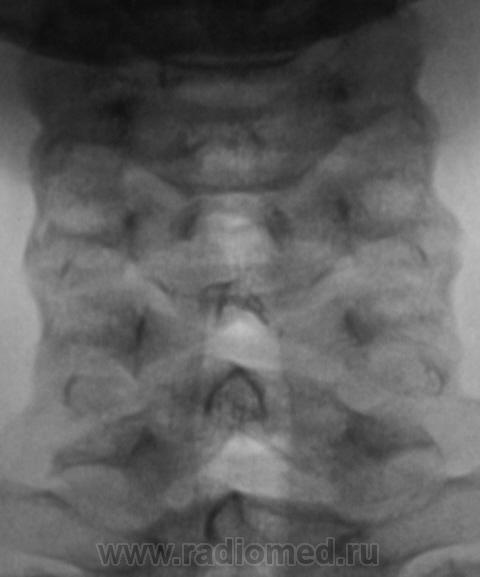

Ребёнок 1о лет.  Произведена рентгенография шейного отдела позвоночника.

Просьба высказать мнение по поводу представленных изображений.

Мы, очень редко сталкиваемся с "детской патологией". Этот случай, конечно, не понятен, да и не понятен он мне, даже после Вашего коммента. Ведь "ступенька" дифференцируется изолировано только по передне-верхнему краю С5. В других позвонках "такого" нет, и все одно "это" считается нормой?

Да, и нижняя замыкательная пластика С4, на мой взгляд, отличается от других нижних замыкательных пластинок тел позвонков, которые "ровные" и четкие. Субъективно, на мой взгляд, патология в сегменте С4-С5 имеется.

Вероятнее всего это что-то связанное с апофизом, возможно, своеобразная остеохондропатия типа Ш.-Мау.

Поддерживаю норму. Хотя нужно заглянуть в рентгенанатомию, и посмотреть сроки ассимиляции апофизов...

Моё мнение - что это вариант развития апофизов, на данный момент не играющий клинического значения.

Аномалия развития - бабочковидный позвонок С5.